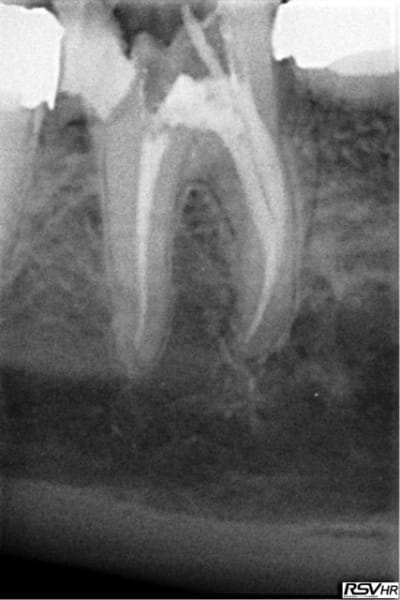

Pour abonder dans le sens qu'il ne faut pas couronner dans tous les cas, voici un cas fait il y a un an.

Les facteurs qui m'ont amené à prendre la décision de faire une endocouronne (proche d'un onlay en vérité) :

- 3 parois solides, la dernière pas trop fine.

- limites toutes supragingivales

- occlusion favorable (pas de photos de l'antagoniste je n'y ai pas pensé)

- patient réceptif

- grande profondeur de la chambre pulpaire (pas très visible sur les photos verticales)

Je n'en fais pas souvent mais quand j'en fait c’est que j'ai confiance. Faire une couronne classique ? Sur ce cas rien que de préparer les limites périphériques et on se retrouve avec une dent à raz la gencive, avec obligation de faire un (ou plusieurs) tenons longs pour une bonne rétention, générateur de fracture radiculaire....

Couronne Emax, collée au Multilink Automix

PS : avant toute remarque, non la patiente ne veut pas que je touche à sa dent de lait résiduelle ;o)